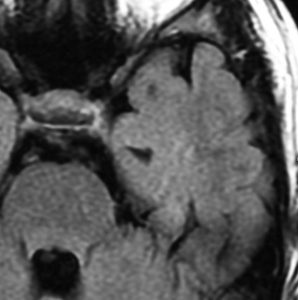

60代の女性に無症候で発見された稀な部位のPXA。結節様ですが脳とのはっきりした境はなく,多房性ののう胞を伴っていました。T2とFLAIR像ではわずかな浸潤像あるいは腫瘍周辺浮腫が疑われます。PXAに特徴的な画像ですが,大脳深部発生でもあり,PXAと画像診断することはできません。定位脳生検術 MRI-guided sterotactic biopsyで病理組織診断を行ない経過観察しました。

3年観察したら嚢胞を伴って増大しました。幸いのう胞性拡大が脳表方向であったのでparietal transcortical approachで全摘出できました。側脳室三角部腫瘍への到達法と同じアプローチですが,この経路では頭頂葉症候を後遺することがありません。

術後は無症状で8年間再発はありません。